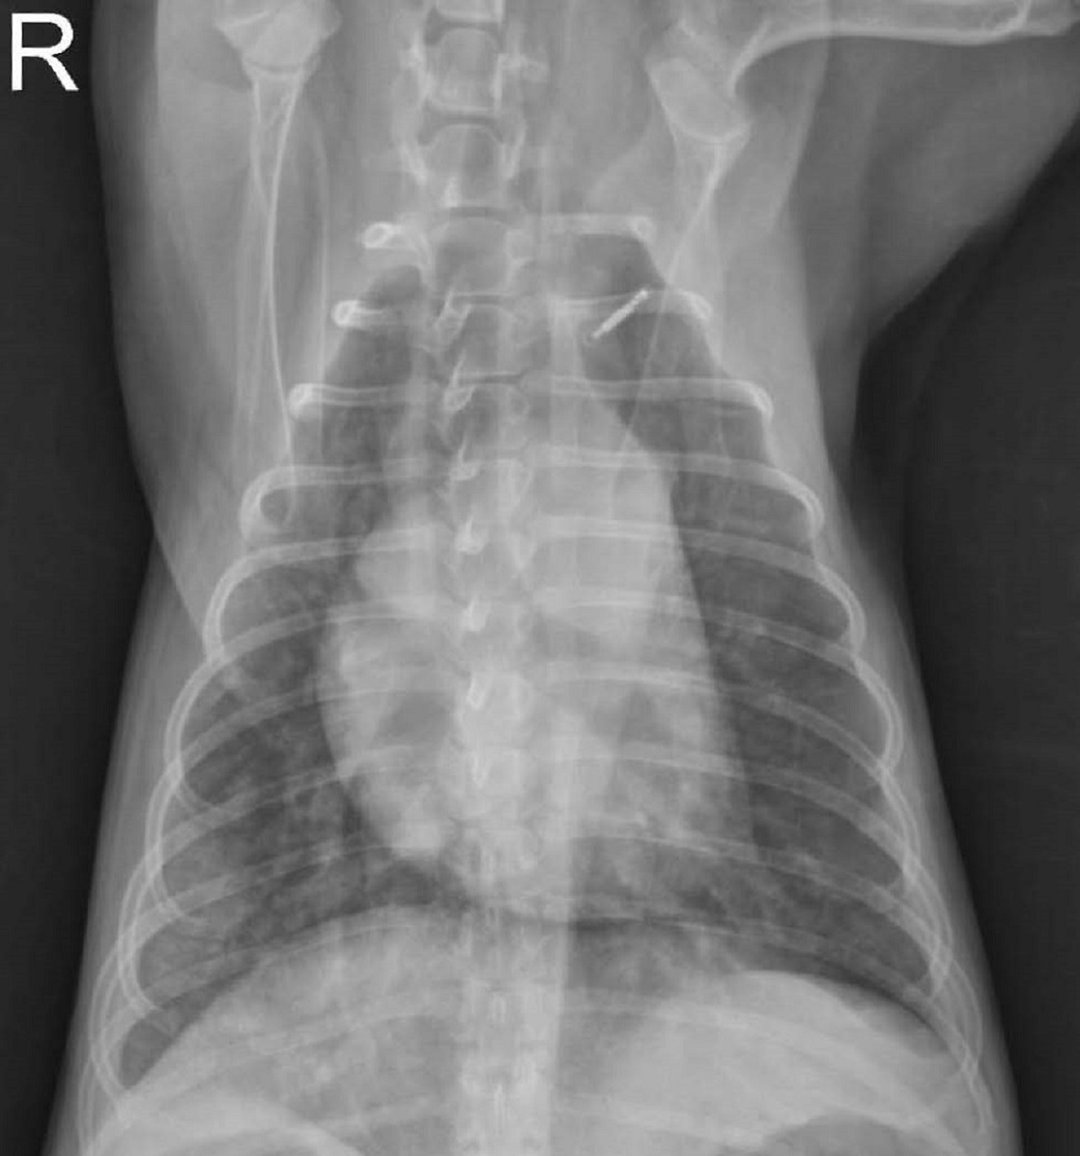

胸部 X 线片可能显示弥漫性或尾背网状结节性肺混浊,可能是由于肺出血。 腹部 X 线片可能正常,也可能显示肾肿大或肝肿大。

由 Katharine F. Lunn 博士友情提供。